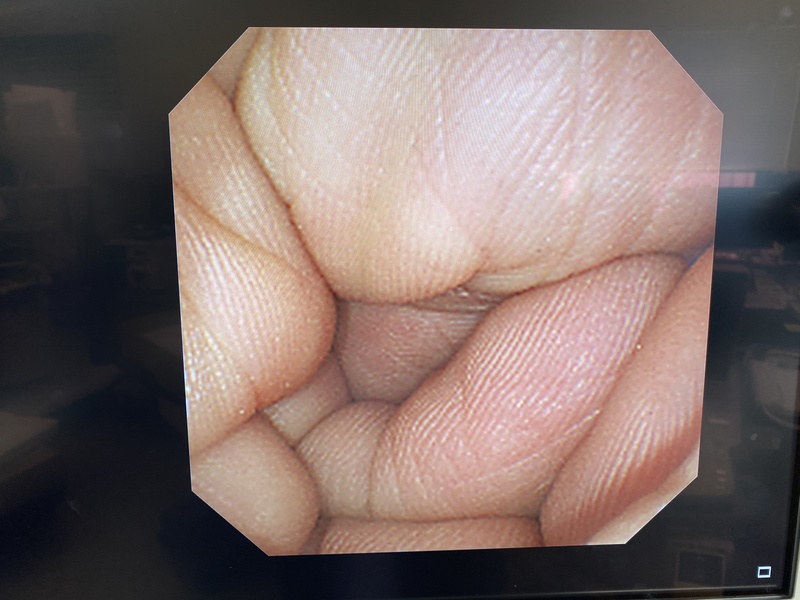

- detail Video Gastroscope / 17392 / GIF-XP260NS